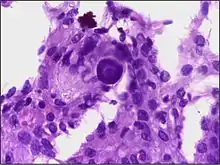

![]() | Plasma cells | Plasma cell showing eccentrically placed round nucleus with cart wheel like chromatin. | Category: Plasma cells | Plasma cell |